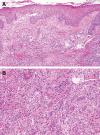

Patient concerns: A 76-year-old male of peculiar skin infection. Metagenomic Next Generation Sequencing and bacterial culture of skin secretions revealed M marseillense. To the best of our knowledge, we report the first patient diagnosed with disseminated M marseillense infection. Here, we identified only 8 other reports of patients with M marseillense infection.

Diagnoses: Disseminated M marseillense infection.

Lessons: Metagenomic Next Generation Sequencing may be a useful tool to diagnose M marseillense infection, but the results should be confirmed by culture and mycobacterial identification.